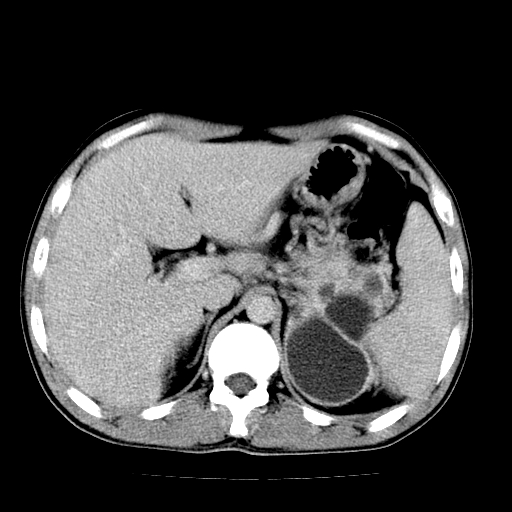

以下是引用天南地北在2007-4-30 13:36:00的发言:[br]支持慢性胰腺炎伴有假性囊肿

以下是引用andymaomao在2007-4-30 14:28:00的发言:[br]支持:1.慢性胰腺炎并假性囊肿形成可能;[br] 2.左肾形态稍增大,旋转不良。